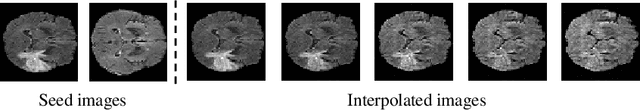

Disentangled representations can be useful in many downstream tasks, help to make deep learning models more interpretable, and allow for control over features of synthetically generated images that can be useful in training other models that require a large number of labelled or unlabelled data. Recently, flow-based generative models have been proposed to generate realistic images by directly modeling the data distribution with invertible functions. In this work, we propose a new flow-based generative model framework, named GLOWin, that is end-to-end invertible and able to learn disentangled representations. Feature disentanglement is achieved by factorizing the latent space into components such that each component learns the representation for one generative factor. Comprehensive experiments have been conducted to evaluate the proposed method on a public brain tumor MR dataset. Quantitative and qualitative results suggest that the proposed method is effective in disentangling the features from complex medical images.